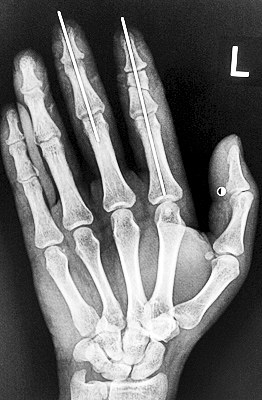

術(shù)后X光顯示,骨骼對(duì)位良好。